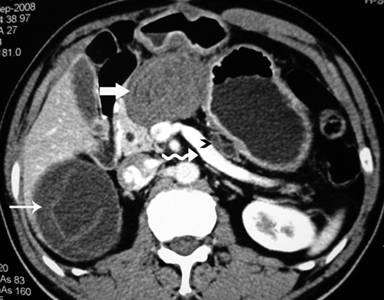

Plain X-ray of the abdomen revealed classical curvilinear calcification in only one patient with a hydatid cyst in the pancreatic body (Figure 1). Ultrasonographic examination which recorded the site, size and extent of the lesions, documented the cystic lesions as anechoic rounded structures in all cases. An abdominal CT scan documented the cysts as spherical hypodense space-occupying lesions. All the lesions were solitary, measuring 26-50 mm in diameter (mean 36.7 mm). Five lesions were cystic with thin walls and one lesion appeared as a multiseptated cyst. Magnetic resonance imaging for defining the lesion and its relationship with the pancreatic duct was performed in three patients (two lesions in the head and one in the body of the pancreas). Two lesions were located in the head (Figure 2, 3, 4, 5), two in the body (Figures 6 and 7) and two in the tail region of the pancreas (Figure 8). In two cases, a preoperative diagnosis was possible due to the presence of classical features which also included a concomitant hydatid cyst in the liver in one patient. All patients underwent surgical exploration; intraoperative cyst puncture for aspiration cytology was successful in three cases (two cases with cysts in the head and one case with a cyst in the body of the pancreas); the results of cytological examination were positive in all cases. A fragmented laminated membrane was observed in two patients, scoliosis in three and hooklets in one patient (Figure 9). The laminated membrane was seen as a foliated, acellular, pale, eosinophilic structure which stained strongly positive with periodic acid Schiff staining and negative with alcyan blue staining. The hooklets had a characteristic shape presenting as a blade, a guard and a root. They were not stained with Papanicolaou stains and their appearance was enhanced by turning down the microscope condenser. There were no complications after diagnostic aspiration. In all three cases, the aspirated fluid was colorless and contained a mean sodium level of 128 mEq/L (range: 128-130 mEq/L), chloride level of 69 mEq/L (range: 65-70 mEq/L) and potassium level of 5.8 mEq/L (range: 5.4-6.3 mEq/L). Cysts in the distal pancreas observed in the two patients were treated by a distal pancreatectomy with splenectomy. Cysts in the body were treated by a pericystectomy in one patient (Figure 10) and a central pancreatectomy in another patient. Cysts in the head region in two patients were treated with evacuation, partial cystectomy and tube drainage of the cavity after protecting the surgical area with a scolicidal solution (Figure 11). Both patients underwent T-tube drainage of the common bile duct; there was rapid regression of the jaundice in these patients. The T-tube cholangiogram confirmed the free flow of bile into the duodenum; the tubes were eventually removed in the third postoperative week. Postoperative confirmation of the hydatid cysts was obtained on the basis of the histopathological findings. There were no postoperative complications; all patients recovered uneventfully. The antihelminthic drug, albendazole, was administered postoperatively (10 mg/kg body weight/day) in all cases for a period of 6 months. All the patients were followed up at three-month intervals and each patient underwent clinical examination, abdominal ultrasonography and indirect hemagglutination tests; no patient had cyst recurrence or dissemination. The mean follow-up time was 58.7 months (range: 4-120 months).

Figure 2. Contrast-enhanced computed tomography scan showing whorled appearance of a hydatid cyst in the region of pancreatic head (thick arrow) causing atrophy of the pancreatic parenchyma with a dilated duct (arrow head) anterior to the splenic vein (curved arrow). Note another hydatid cyst in segment VI of the liver with separation of the membranes (thin arrow) (Patient #5). |

Figure 3. T2-weighted magnetic resonance image in the same patient showing a hypointense hydatid cyst in the pancreatic head (thick arrow) causing dilatation of the pancreatic duct (curved arrow) and separation of the membranes in the hepatic hydatid cyst (thin arrow) (Patient #5). |